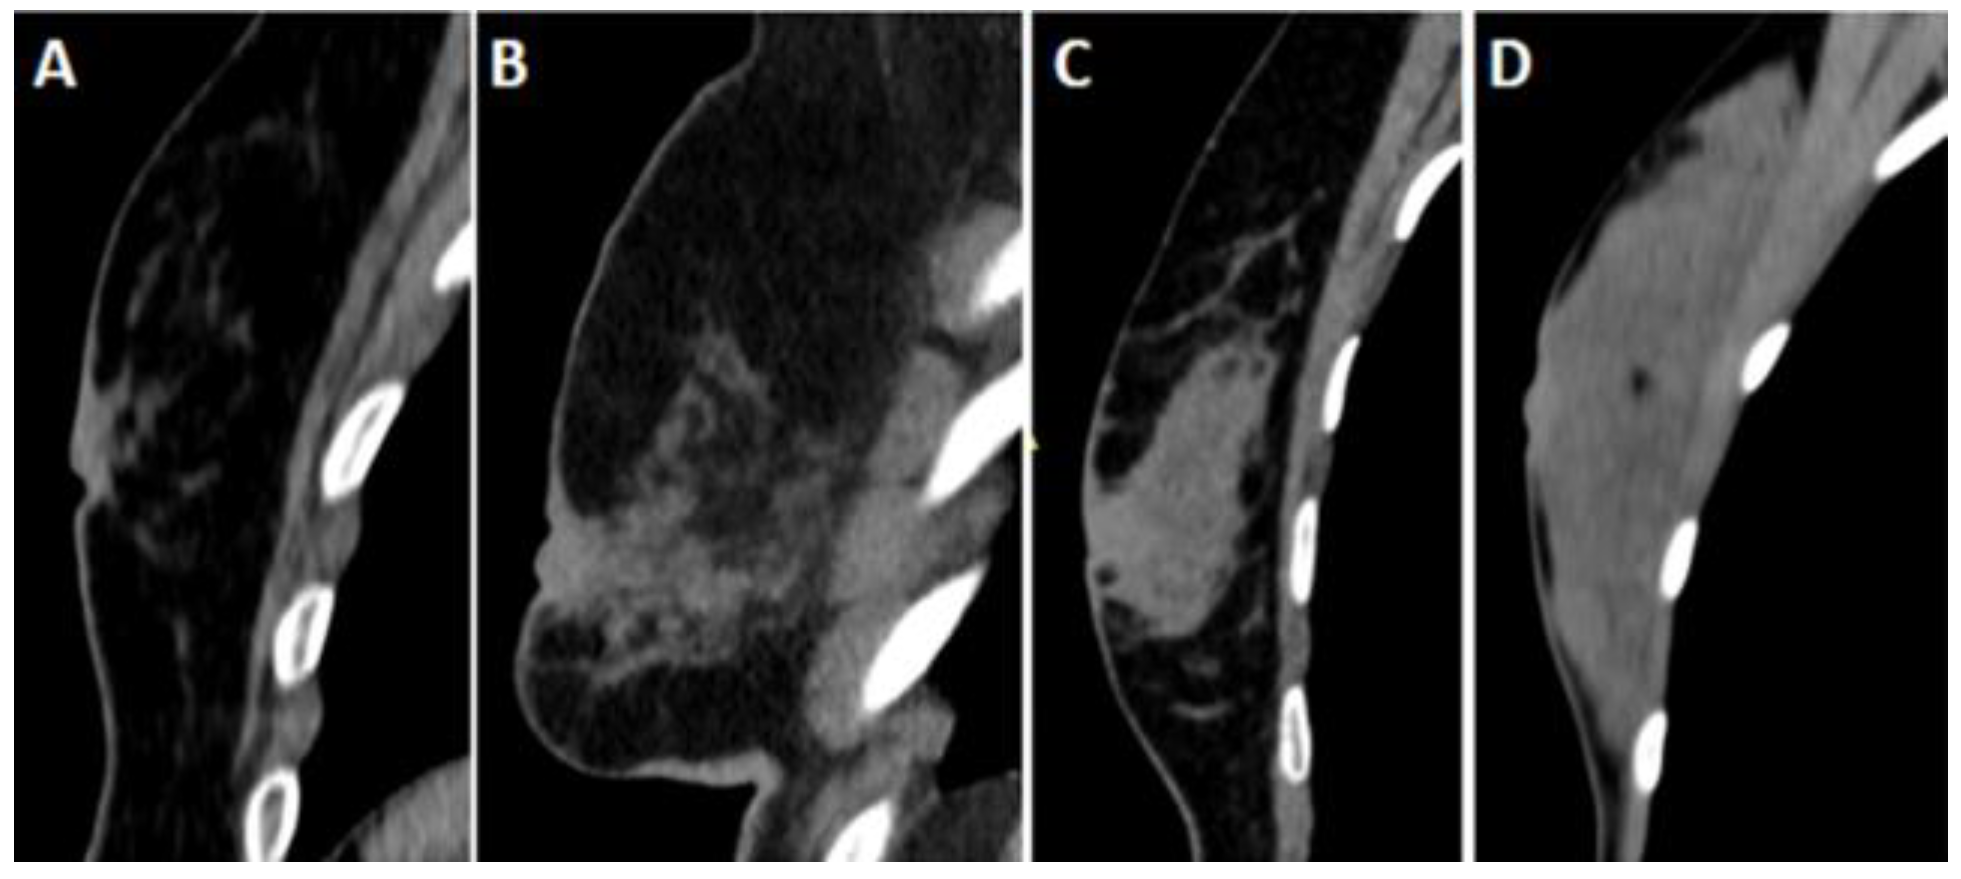

Breast densities were evaluated on sagittal reformat CT images based on the American College of Radiology (ACR) breast magnetic resonance imaging definition (Figure 3). ACR densities of A and B were accepted as fatty, and ACR densities of C and D were considered dense patterns.

Figure 3. Breast densities on CT images were evaluated using sagittal reformat images.